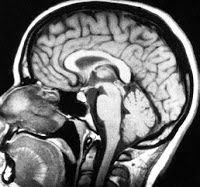

The baby was kept in the machine for several minutes to generate baseline data of the normal metabolic activity in the brain. This was used to compare to the data gathered during and after the surgery. Analysis of the MRI data indicated that the surgery subjected the infant to significant trauma. The greatest changes occurred in the limbic system concentrating in the amygdala and in the frontal and temporal lobes.

A neurologist who saw the results to postulated that the data indicated that circumcision affected most intensely the portions of the victim's brain associated with reasoning, perception and emotions. Follow up tests on the infant one day, one week and one month after the surgery indicated that the child's brain never returned to its baseline configuration. In other words, the evidence generated by this research indicated that the brain of the circumcised infant was permanently changed by the surgery.